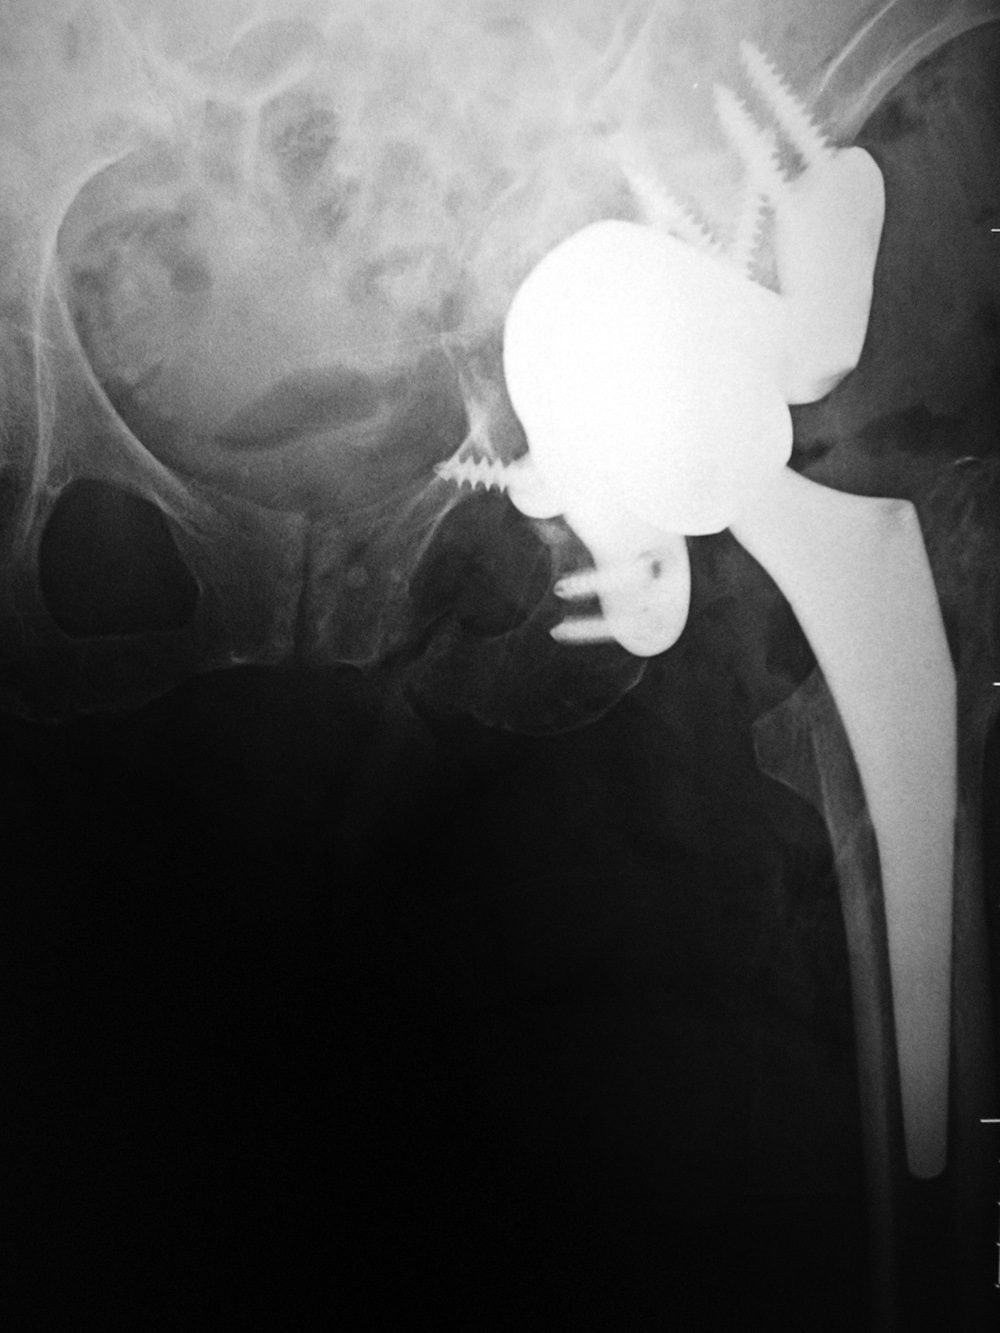

Triflange acetabular component total hip revision arthroplasty with long femoral stem |

Triflange acetabular component total hip revision arthroplasty |

83 year-old woman |